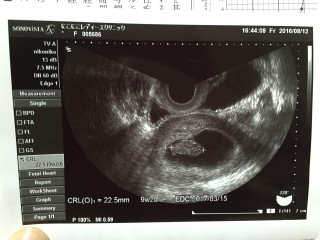

予定日確定。 赤ちゃんも22mmで順調 次の検診は2週間後 楽しみだな~(¨)

初めての妊娠!10日前に心拍確認できましたが出血ありで切迫流産と診断され、不安な毎日でした。 でも今日前回の倍の大きさ、22ミリに成長!まだ8週6日かと思っていましたが思ってたよりも大きくて安心!母子手帳のための書類ももらいうれしさいっぱいで涙が出ました。次は4週間後!無事に大きくなりますように。

2回目の検診です!初診から3週間くらいが経ち、赤ちゃん無事なのかすごく不安でした...。最終月経日から数えると8w2dのはずだったんですが、先生は「ちょっと大きいね~9w2dの大きさだから大きさで予定日決めるね~」と言われました。このとき初めて心臓と赤ちゃんが動いてるのを見て感動しました。明日また検診があるので楽しみです☆

9w2dだそうです(^^)2週間前は、たった2mmしかなく、ちょっと心配でしたが、なんと22.7mmと、10倍ぐらい大きくなってました!小さな心臓の音もはっきりと聴こえて、元気に育ってるみたいで安心しました。次の検診が待ち遠しいです(^^)